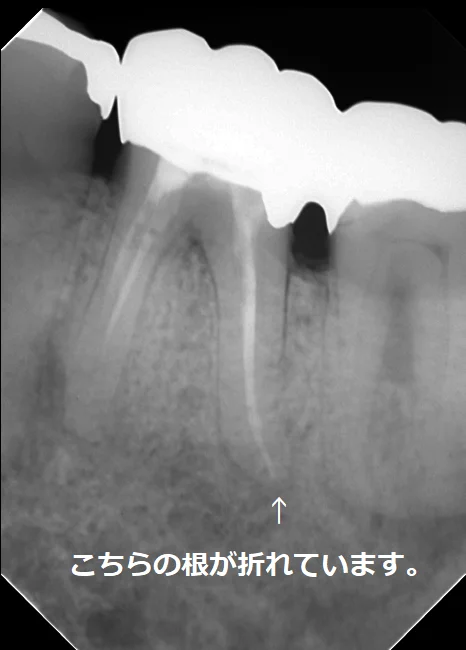

歯の抜歯の原因の一つである歯根破折についてです。

歯根破折というのは、力に耐えられず歯の根が折れてしまうことです。(こちらの記事でも書きましたね。)

神経の治療を行う事で、健康な歯の部分が減ってしまい、力に耐えきれなくなってしまう事があります。

また、一昔前までは・・・

こーんな感じで

「神経の治療後はメタルコア(金属の土台)を入れる」

というのが歯科界での常識でした。

当然金属は歯よりも固いので、噛む度に楔のような作用が働き、歯が折れる主たる原因となってしまっていました。

こちらの方は私が治療に入った時にはファイバーコアが入っていましたが・・・

その前は太いメタルコアが入れられていたそうです。

実際に被せ物を除去して根の状態を直接肉眼で確認したところ、後ろ側の根がレントゲンには写らないラインで真っ二つに折れていました。

今回の場合も2本の根の管があるように最初のレントゲン上では写っていましたが、実際にはその2本は非常に細い道でつながっており、しかも元々の根の管がその細い道の中に隠れていました。

最初のレントゲンに比べると神経の治療後の薬が根の先まで綺麗に入っているのが分かるかと思います。